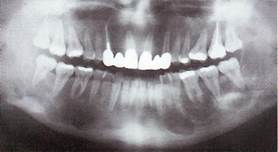

R-картина. Рентгенологиче­ская картина проявляется в виде истончения кортикального слоя и выбуха­ния его кнаружи, определяется множество кистовидных просветлений.